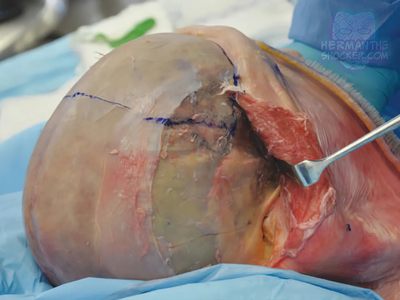

Composite facial allografts have become increasingly popular in the reconstruction of complex facial defects. Good to excellent aesthetic results can be achieved, particularly when a foundation of donor skeleton has been transferred...